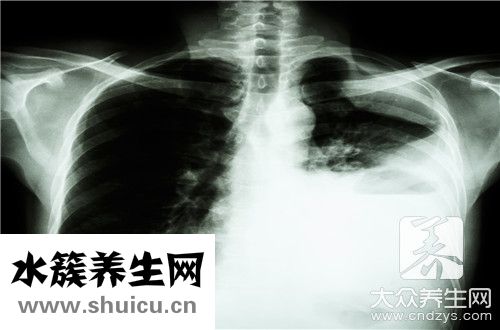

肺鈣化灶是肺實質肺細胞發炎后產生的“疤”,一般無生命危險,一部分病人可能和肝內膽管結石病人一樣會出現肺區悶脹覺得,如診斷一般不需醫治,肺內有鈣化點可能是肺內膽壁厚一部分增厚。肺內血管影。

一切正常肺組織是由支氣管、支氣管炎支氣管、淋巴結、血管等構成,呈淡粉色。若有非常總數和毒力強的結核菌入侵肺組織并在里面生長發育繁育,造成新陳代謝物質,使肺組織受到損壞,出現仿佛霉變的乳酪一樣的物質,使一切正常的肺組織構造、生理作用消退。醫藥學上稱之為奶酪樣壞死。壞死物偏重于酸堿性,不容易汽化消化吸收,能長時間具有。在機體抵抗力強,或是放療后,奶酪樣疾病中的結核菌新陳代謝消沉,繁育工作能力被消弱,疾病缺水而干躁,碳酸氫鈣和碳酸鈣粘附產生增厚。

實際上,大家每日吸氣的氣體里都可能帶有結核菌,因而感染結核菌也是很普遍的。只不過是大部分人到感染了結核菌之后,自身的人體抵抗能力十分強,因此沒有生病,沒有主要表現出病癥,這稱為潛在性感染。僅有少數人感染結核菌后,會發展趨勢成肺結核。很多人去做透視,發覺肺臟有鈣化點,這就表明其感染過結核菌。此外,一般的肺結核病人治愈后,肺臟也會留有鈣化點,事實上,肺部鈣化點是肺結核治愈的方式之一。

肺臟別的感染性的發炎也是這般,例如得了肺炎的情況下,歷經醫治,造成 發炎的病菌、病毒感染被殺掉了,但肺上也會留有鈣化點。

因此,一般來說,肺部鈣化點是良好的,只意味著以前的變病,對人體沒什么影響,不必太在意,更不必醫治。